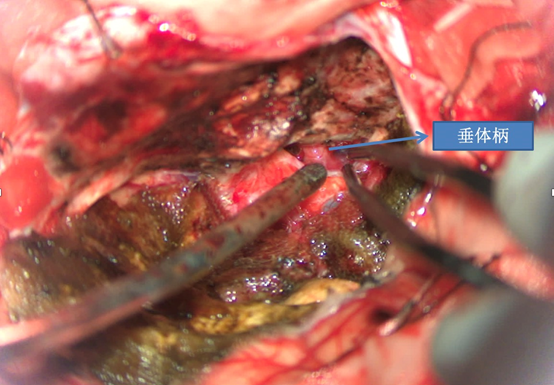

前颅窝底脑膜瘤常起源于前颅底筛骨筛板处的硬膜,瘤体多为双侧生长,少数为偏侧生长,女性稍多于男性。肿瘤可累及鸡冠和蝶骨平台的任何区域,是前颅窝肿瘤中最多见的一种。因为肿瘤位于前颅窝底,额叶在功能上属于“哑区”,患者就诊发现肿瘤时瘤体多已巨大。主要症状可有颅内压增高症状、视力减退、癫痫以及精神症状等。该患者主因“左眼失明10个月,头痛3个月”就诊。术中采用双额冠状开颅,左侧为主,由于肿瘤体积巨大,术中切除少许薄层额叶脑组织,边离断基底、边瘤内减压,分块切除肿瘤,最终探查肿瘤基底主要位于鸡冠、筛板、蝶骨平台、鞍结节、前床突处硬膜,术中见肿瘤供血主要来源于前颅窝底硬膜及大脑前动脉分支,术中仔细辨认供血动脉、过路血管,大脑前动脉及其分支保护完好,术中见视神经、视交叉受压明显,尤其是左侧视神经已缺血苍白,最终达Simpson II级切除。术者体会,该患者术前行多模态重建,可见瘤表数条粗大的静脉,术中切莫过早离断肿瘤的引流静脉,以防因引流不畅致瘤体肿胀出血;术前行多模态重建,利于鉴别供血动脉、过路血管,早期离断供血动脉更利于肿瘤切除;该类肿瘤基底一般较为广泛,不能盲目离断基底,尤其是近鞍结节处,可以于中线处离断基底,进入第一间隙后向两侧探查并保护视神经,待充分缩小瘤体看清楚毗邻的血管神经后再将其完全切除;术毕做好多层颅底重建以防脑脊液漏。另外,该患者术前左眼失明已达10个月,术后第1天即有光感,术后1月复查左眼视力可达50cm内数指,这在临床中非常少见,对于此类病人,不要轻易放弃挽救视力的任何机会。